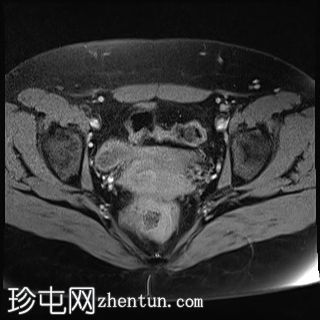

轴位

T2加权像

4.jpg

T1加权像

7.jpg

8.jpg

9.jpg

双侧卵巢位置接近(卵巢相吻),左侧卵巢内可见一边界清晰的囊性病变,大小约3.1 × 2.7 × 2.9 cm,T1加权像呈高信号,T2加权像可见暗点征及内部暗点征。以上MRI特征符合卵巢子宫内膜异位囊肿的诊断。

右侧卵巢可见一囊肿,大小约为 2.8 × 2.0 × 2.2 cm,T1 加权像呈高信号,囊内可见液-液平面,提示囊内含有不同时期的出血性物质。由于对侧卵巢存在典型的子宫内膜异位囊肿,且该囊肿无强化,影像学表现强烈提示为另一子宫内膜异位囊肿。

双侧卵巢均可见多个小卵泡。